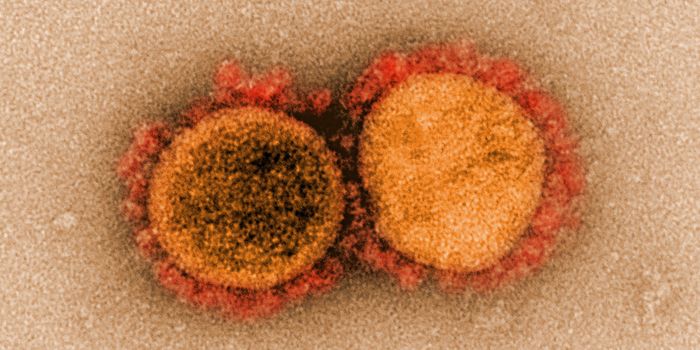

JUL 05, 2020Cell & Molecular BiologyThe pandemic virus SARS-CoV-2 enters the body through the respiratory system to cause the illness COVID-19. But we know ...

MAR 18, 2020MicrobiologySARS-CoV-2 is a coronavirus that causes an illness called COVID-19. There are now well over 210,000 confirmed cases worl ...